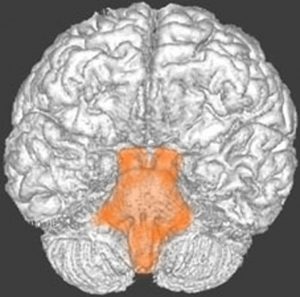

- 脳の底面からしか見えないのでいろいろな角度から見ています

これは脳の中心部を縦切りにした写真です。脳幹部は上から順に,中脳 midbrain (黄色),橋 pons(オレンジ),延髄 medulla oblongata(ピンク)と呼ばれます。

共通しているのは脳幹部の障害では意識障害が出ることです。中脳脚から延髄腹側まで錐体路という運動神経を司る経路があり,これが障害されると片麻痺や四肢麻痺がでます。脊髄視床路の障害では全身の感覚障害となります。主として背側損傷では運動失調も出ます。脳神経麻痺,眼球運動障害,嘔吐などさまざまで複雑な症候が出る重要な部位です。